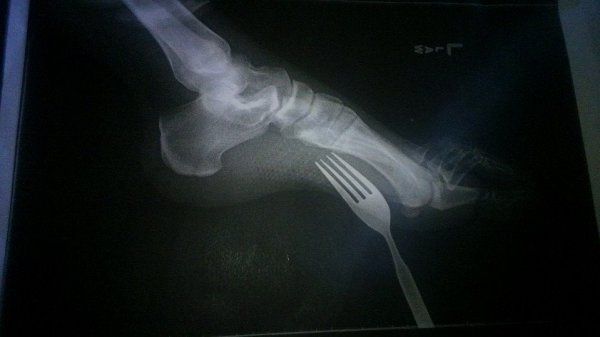

На это зрелище немного больно смотреть